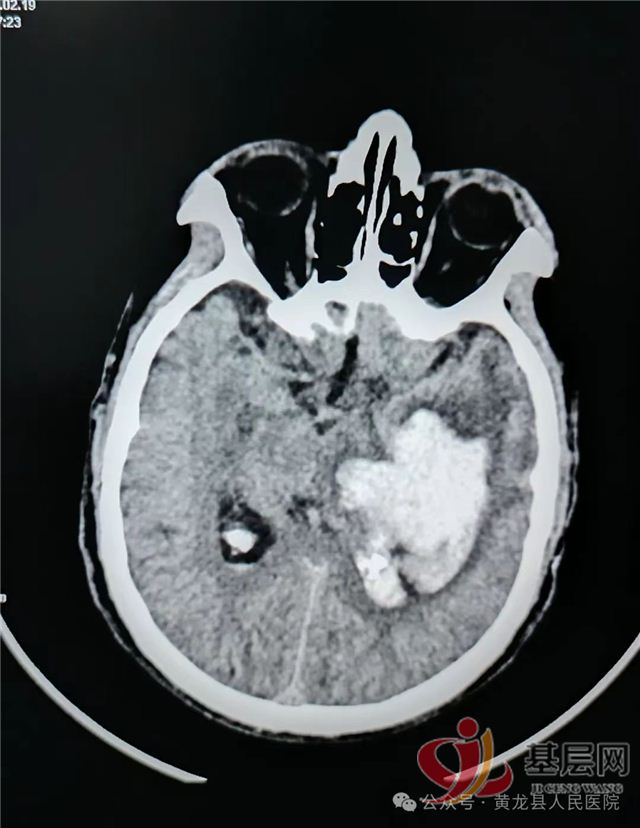

术前CT:左侧内囊--丘脑区脑出血破入脑室,出血量巨大,同侧大脑半球受压明显,脑室挤压,中线偏移